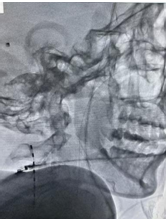

▲ 短时程脊髓电刺激电极置入术,正侧位透视片